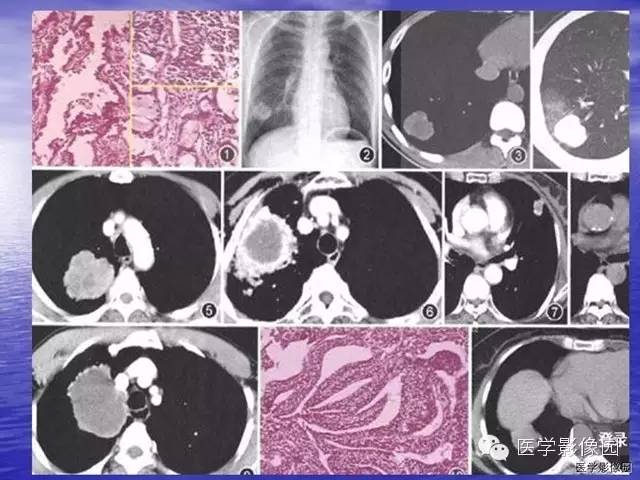

【病例】巨大中央型肺癌1例